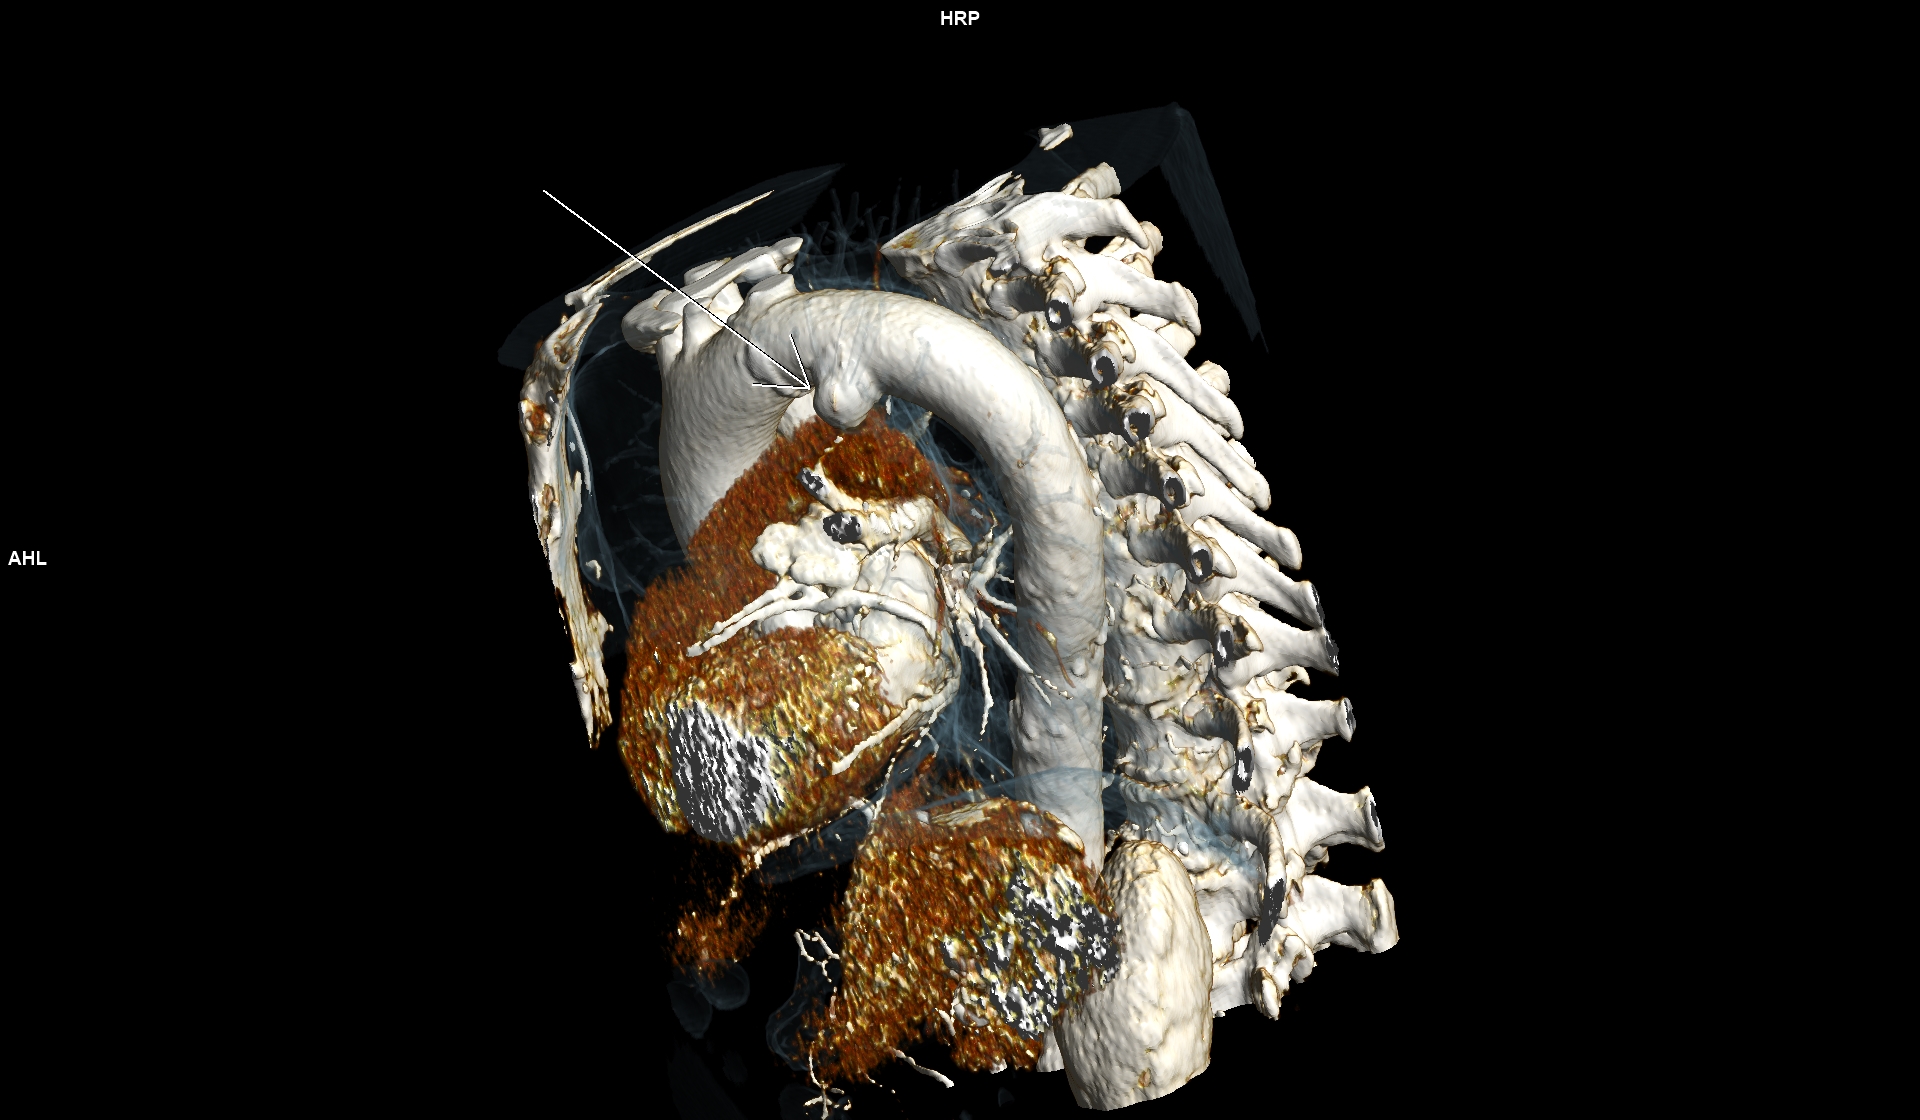

Figurile 3, 4, 5 si 6: reconstrucție volumică din achiziție angio în timp arterial – aorta toracică

Discuţie caz nr 102: Ductul arterial este o structura de by-pass între aorta descendentă și trunchiul de arteră pulmonară care funcționează în viață intrauterină deoarece plămânii nu sunt aerați; în mod normal se închide în primele zile după naștere. Imaginile prezentate arată că ductul arterial este închis însă se evidențiază creșterea calibrului unei reminiscențe a ductului arterial la deschiderea în aorta descendentă.

DE LUAT ACASĂ!!! Inserția ductului arterial în aorta descendentă toracică este util să fie cunoscută deoarece dacă avem canal arterial permeabil acesta poate fi de dimensiuni mici și poate să nu cauzeze probleme semnificative rămânând nedetectat – practic descoperire întâmplătoare.